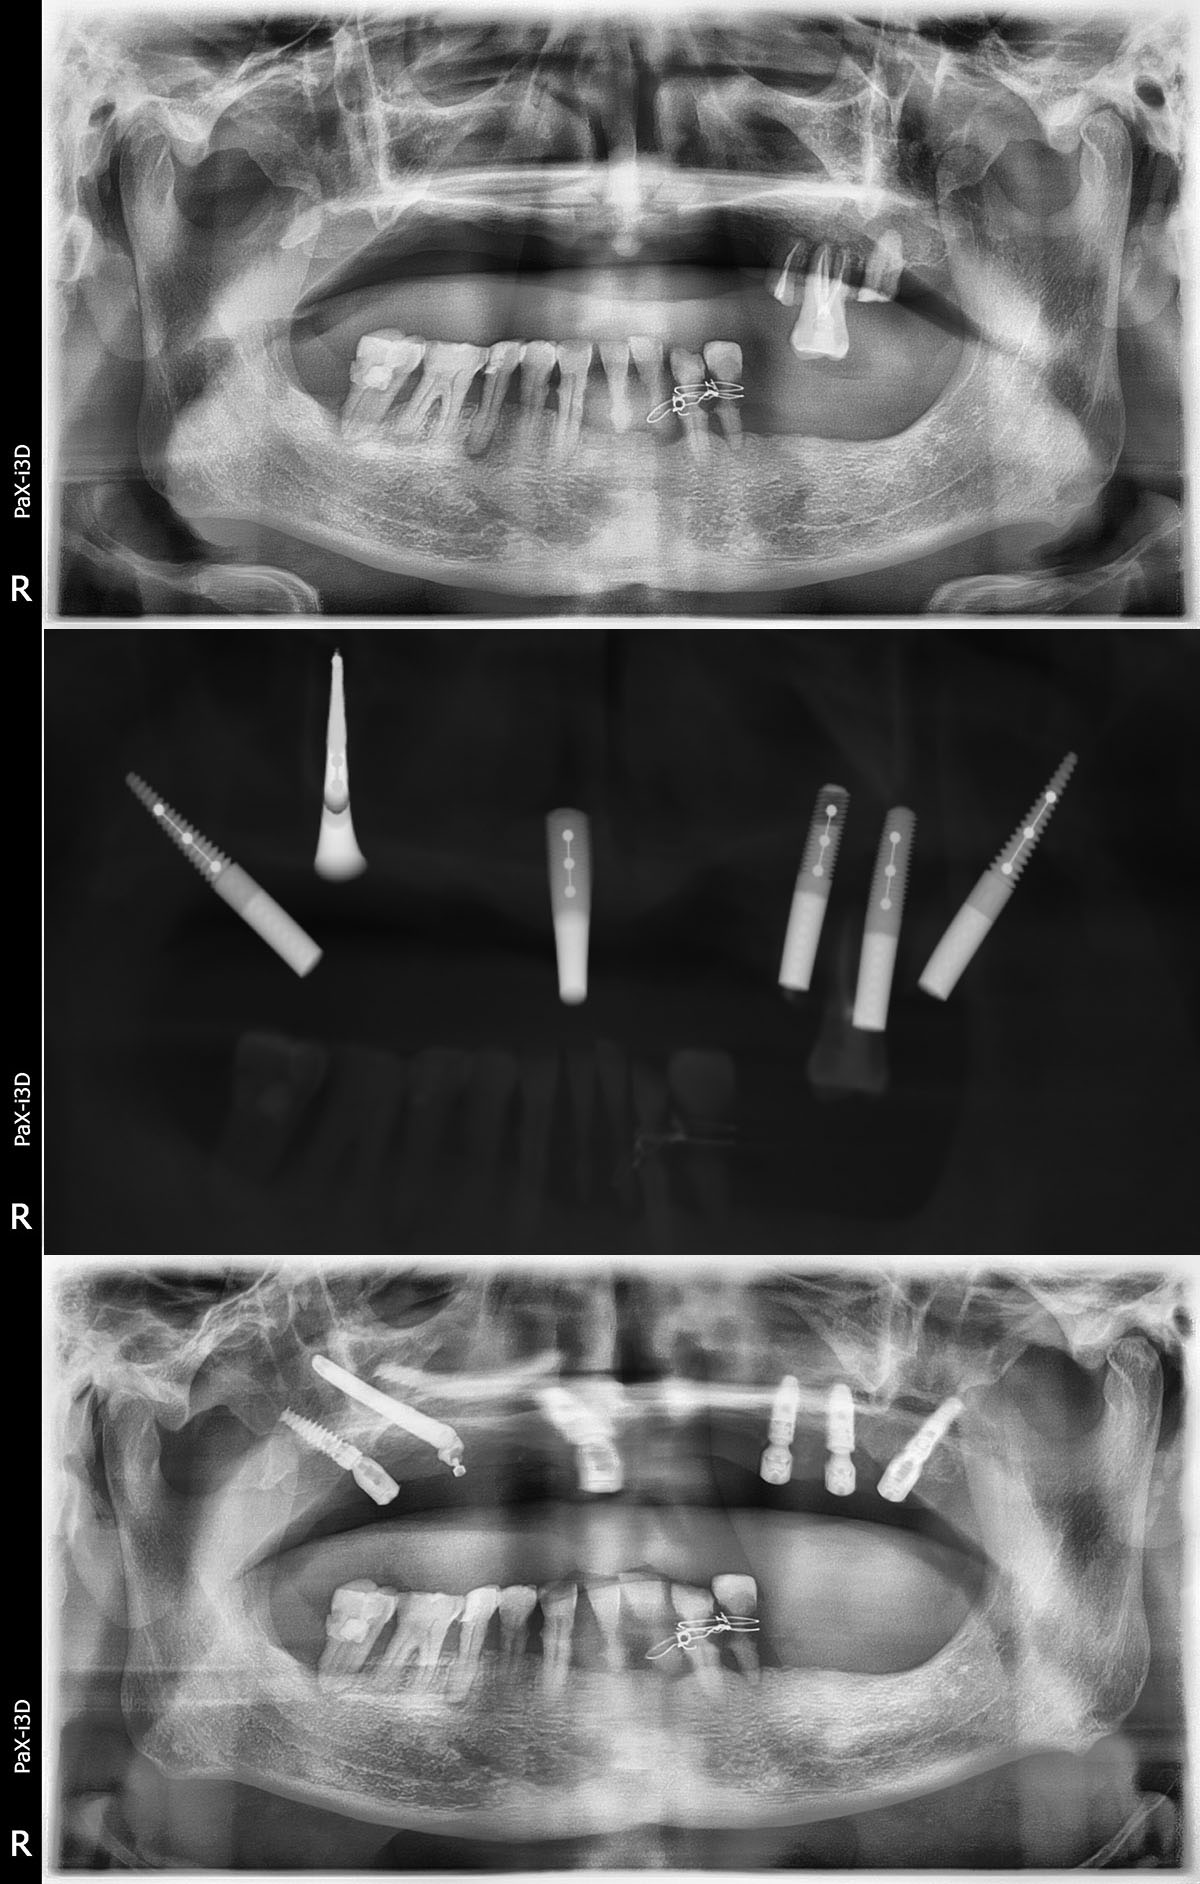

种植牙是缺失牙的常规修复手段,刘先生咨询了多家医院,很多医生对他的口腔状况都束手无策。并得出了一致的结论:上颌牙槽骨极度萎缩,按传统的种植方法,不仅操作难度极大,而且术后恢复比较缓慢,种植体也很容易失败。这让刘先生十分无奈。在四处打听的过程中得知,贝臣齿科国际牙种植中心团队正是国内为数不多掌握穿颧种植术的团队。经过详细的检查和问诊后,得知可以通过穿颧种植手术解决缺牙问题,让他很是欢喜。

穿颧种植术是一种可靠的修复方法。其主要优点是避免了大量植骨手术,缩短了治疗周期。颧种植体从后牙区牙槽嵴顶或偏腭侧植入,穿上颌窦进入颧骨,获得颧骨与上颌骨双重固位;同时在前牙区植入2至4枚常规种植体,可完成上颌无牙颌的固定修复。

通过术前检查的CT片以及检测结果,传统“一日得”种植术不适合刘先生,贝臣医生团队量身定制穿颧半口高难度治疗方案来帮助刘先生恢复一口好牙!穿颧种植方案就是贝臣医生团队经过分析后最终给出的治疗方案。事实上能做这一种植方案的医生“穿颧种植方案”少之又少。经过贝臣医生团队帮助刘先生实现重获新牙的愿望。

“穿颧种植体的长度是传统植体的3~4倍,因此起点的微小误差就可导致末端的严重偏离,所以术前应详细进行手术计划,CT检查对于了解双侧颧骨的情况必不可少。患者还应进行常规的全身及口腔颌面部的专科检查,排除相关禁忌症的存在。”